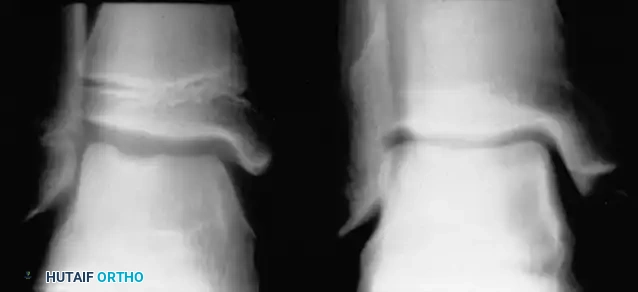

Clinical Pearl: To differentiate MED from Perthes disease, evaluate the bone age. In Perthes disease, the bone age typically lags 1 to 2 years behind the chronological age. In contrast, bone age usually remains normal in multiple epiphyseal dysplasia. Furthermore, radiographs of the ankle in MED often reveal characteristic lateral narrowing or wedging of the distal tibial epiphysis.